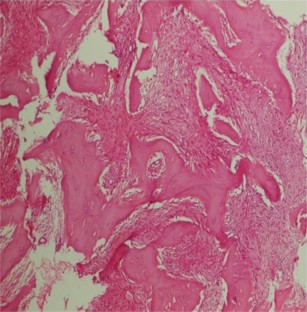

A rare case: sclerosing osteomyelitis of the frontal bone

The patient presented in this study had a form of chronic sclerosing osteomyelitis (CSO) that is rarely reported in calvarial bones and has never been reported in the frontal bone in the literature. We aimed to contribute to the literature with this case study. In this study, we report a 14-year-old girl who presented with swelling and pain in the frontal bone and underwent treatment due to CSO. The patient had no history of trauma and chronic infection. We conclude that CSO should be considered in the differential diagnosis of the patients presenting with cranial swelling whose diagnosis cannot be established based on the radiological findings.